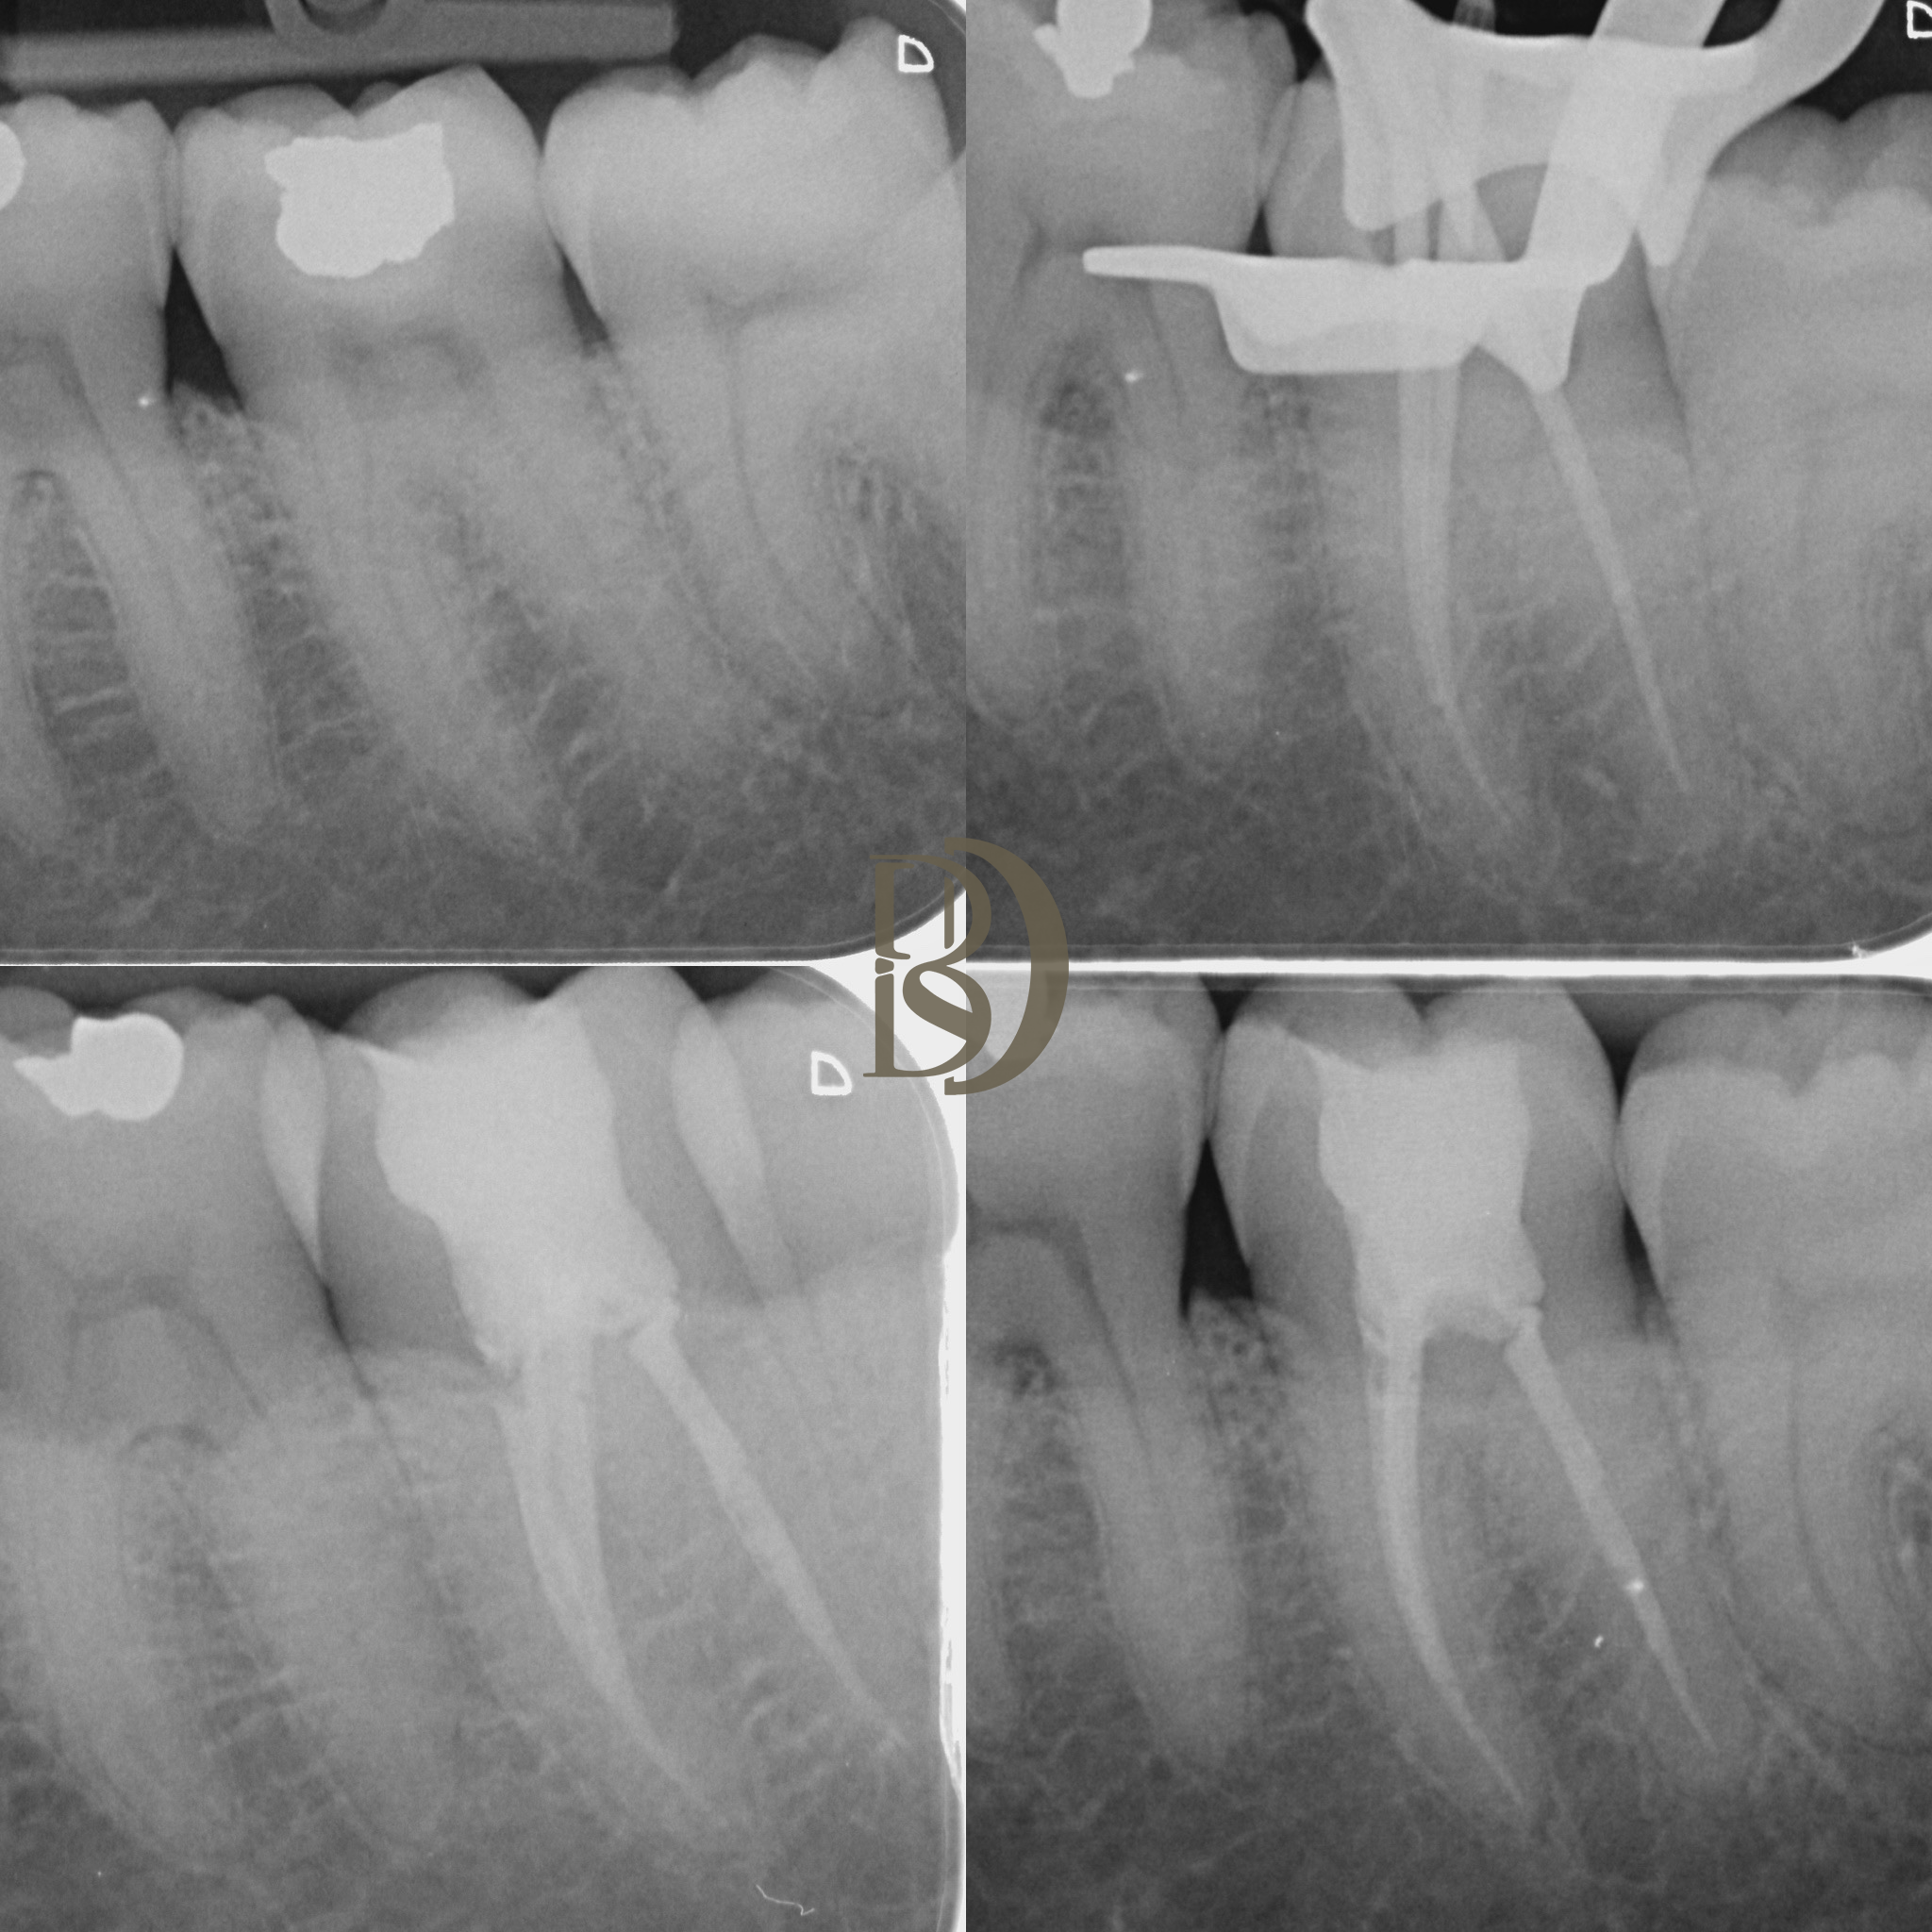

Some examples of Dr Fred’s Endodontic cases:

Dental X-ray showing teeth with root canals and dental crowns.

Dental X-rays showing root canal treatments on several teeth.

X-ray of dental treatments including root canals and fillings

Dental x-rays showing root canal treatment with dental fillings